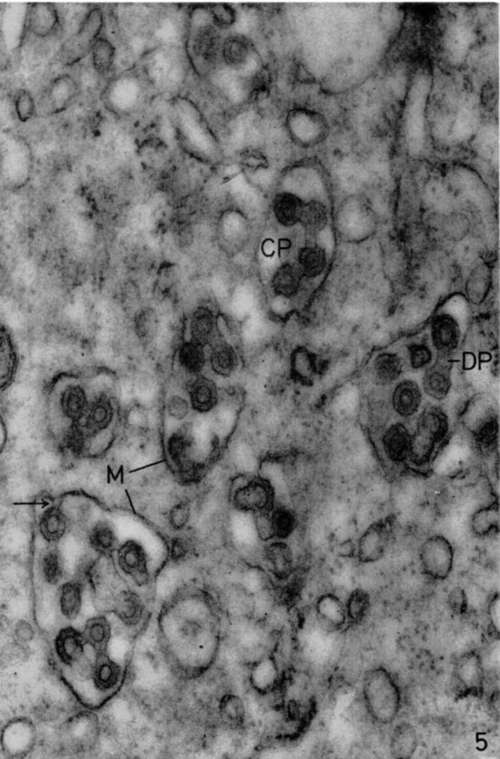

Figure 5. Bone marrow of leukemic mouse. No lead hydroxide staining. In cytoplasm of megakaryocyte numerous vacuoles are seen containing many viruses. These viruses appear to be budding (arrow) from membrane limiting cytoplasmic vacuoles (M) by same process observed at level of cell membranes of leukemic cells. Structure of these viruses is identical to that of viruses observed in intercellular spaces of leukemic organs. The only particularity is the frequent occurrence of dumbbell (DP) or chainlet (CP) profiles resulting from the continuity between outer shells of several viruses. X 84,000.